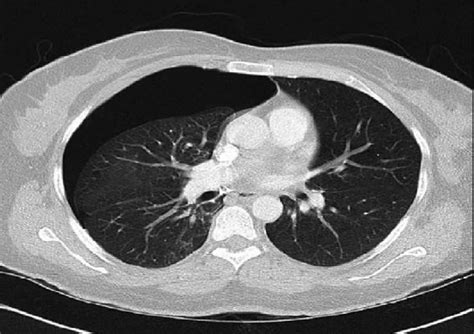

Loculated pneumothorax | Image | Radiopaedia.org

Loculated pneumothorax | Image | Radiopaedia.org from images.radiopaedia.org